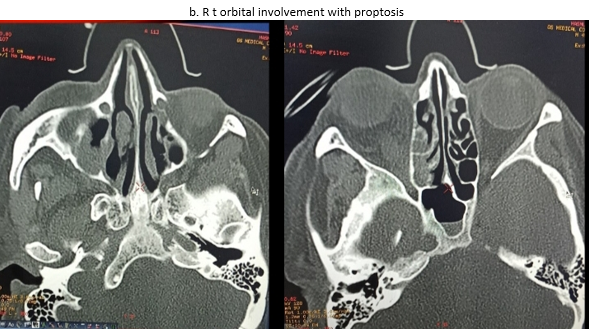

Rhino-orbito-cerebral is the most common clinical subtype of disease. Mucormycosis is a difficult to diagnose rare disease with high morbidity and mortality.[3] This form presents with sinusitis, facial and eye pain, proptosis, progressing to signs of orbital structure involvement.[4], [5], [6], [7] Necrotic tissue can be seen on nasal turbinates, septum and palate. This may look like a black eschar.[7], [8] Intracranial involvement develops as the fungus progresses through either the ophthalmic artery, the superior fissure, or the cribiform plate.[4], [5], [6], [7]

Patient presented during 14th April 2021 midnight- 31st May 2021 midnight. COVID 19 RT PCR positive at any time during the study period or within 28 days before beginning of study period. Biopsy proven mucormycosis and/or patient had features clinically consistent with diagnosis of mucormycosis, that is, two or more of following on presentation: Black eschar within oral cavity and/or blackish eschar within nasal cavity and/or blackish eschar over face severe facial pain and facial swelling of onset within last 28 days. Eye swelling and/or ptosis and/or proptosis Computerised tomography or magnetic resonance and imaging suggestive of invasive fungal rhinosinusitis.